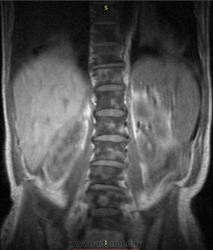

Случай несоответствия рентгенологической картины и данных МРТ при поражении костного мозга.

К сожалению без документов, расказываю по памяти: Мужчина 1958 года рождения, поступил с жалобами на боли в животе, перфорация полого органа прооперирован, гистология, болезнь Крона. Лихорадка около 6 месяцев до 39С, снижающаяся при терапии гормонами, двусторонний гидроторакс, анализ плевральной жидкости нечего. В подмышечной области единично увеличеный лимфузел, пункция, нечего не найдено. На МРТ забрюшинного пространства инфильтрация костного мозга, пункция грудины, ничего. Посмертно, гистологически подтвержденный диагноз лимфогранулематоз.

При таких заболеваниях, на стади докомпрессионных переломов тел позвонков, очень трудно на рентгенограммах заподозрить системную инфильтрацию костного мозга.